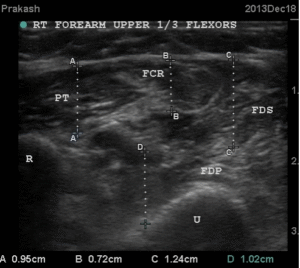

The USG images on 6th December show that there are no clear outlines for muscles which are hyper echoic. The same hand on December 18th after 6 sessions of USGDN shows return of clear muscle outlines, with islands of hypoechoic muscle tissue in the hyperechoic fibrotic mass.